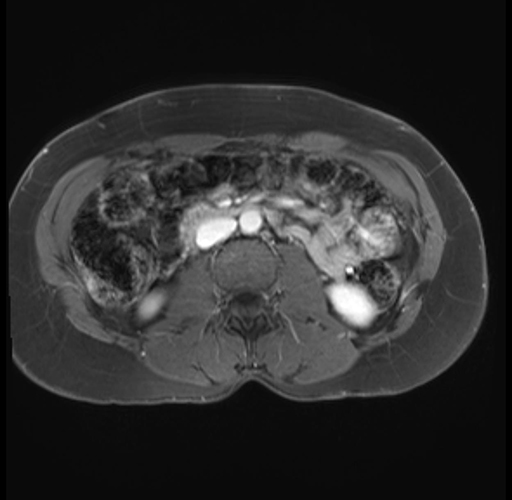

Imaging Analysis

Look through the patient's CT scan to identify any areas of concern for the necessary procedure.

Based on your CT findings, which issue(s) are present and would give reason for "planned slowing down moment(s)" in this case?